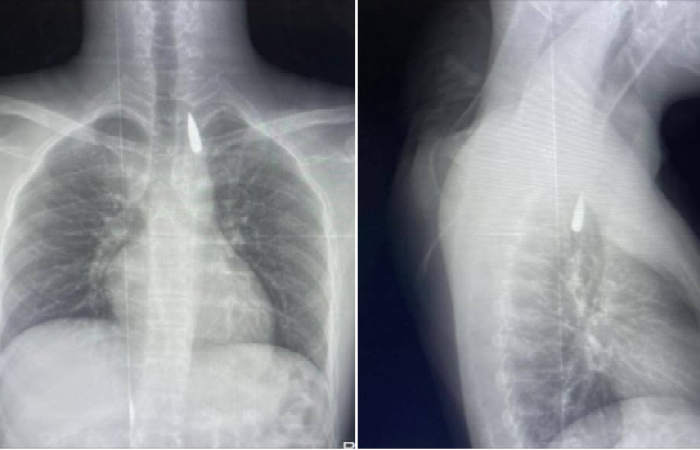

من جانبه، أوضح الدكتور تامر عبد الله، عميد كلية الطب ورئيس مجلس إدارة المستشفيات الجامعية، أن العملية أُجريت يوم 21 أكتوبر 2025، موضحًا أن المصاب من قطاع غزة كان قد تعرض لإصابة بطلق ناري في الرأس، استقر المقذوف على إثرها داخل تجويف القفص الصدري بالقرب من الشريان الأورطي، وهو من أخطر المواقع في جسم الإنسان.

ورغم دقة الحالة، نجح فريق من أطباء جراحة القلب والصدر والتخدير والمعاونين في استخراج المقذوف بأمان وإنقاذ حياة المريض، في إنجاز يُضاف إلى سجل المستشفيات الجامعية بالإسكندرية في مجال الجراحات الدقيقة.